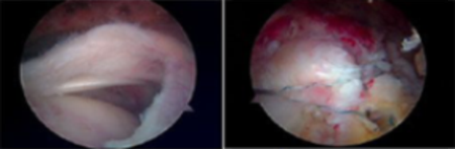

관절경 수술(Arthroscopy)

- 관절경이란 가느다란 관 끝에 부착된 특수렌즈를 관절 속에 넣어 관절 내부를

외부 모니터 영상으로 확인하는 장비입니다.

대부분의 관절 질환은 관절경으로 진단과 동시에 수술이 가능합니다.